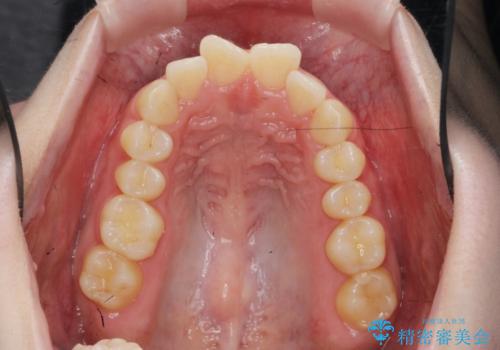

マウスピース 狭窄歯列の改善

- 噛み合わせが深い、笑った時の歯並びの改善を求めて来院されました。

マウスピース型の矯正装置インビザラインを用いた治療を計画します。

狭くなってしまった歯並びを放物線状に並べることで噛み合わせの安定・見た目の改善・ガタつきの改善を達成することができました。